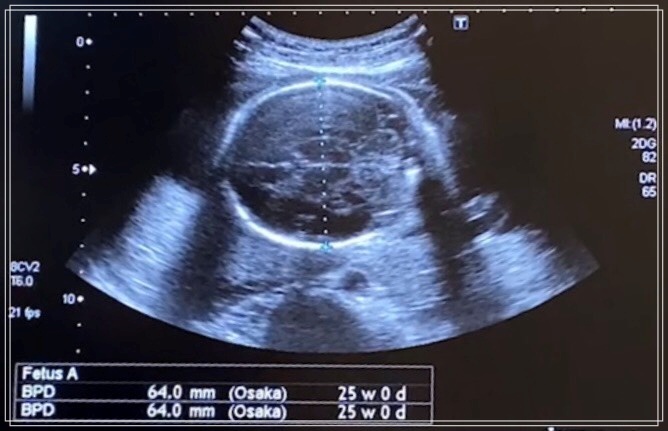

チビきっきんは、頭のサイズが64mmで体重が891gで順調に育ってました。

今回はエコーの様子もご紹介します。

頭の大きさ、体重もわかるのがすごいなと思いました。

順調に育っているとも検診の結果言われましたので安心できました。